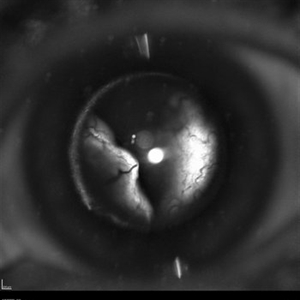

Iris Bombe

Sep 15 2020 by Sophia El Hamichi, MD

A 23-year-old female with Coats' disease OS.

Photographer: Belinda Rodriguez, Murray Ocular Oncology and Retina, Miami

Condition/keywords: Coats' disease, iris bombe, silicone oil